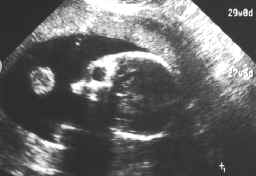

Here's some echo-pictures of Georgy before he was born:

fetus-29-10-98.jpg (88503 bytes)

29 October 1998